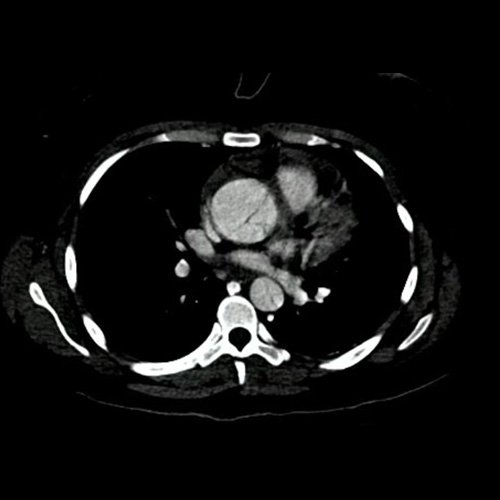

Angiotomografía con contraste endovenoso de aorta toracoabdominal. Corte coronal.

• Angio-TCMS de aorta toracoabdominal y vasos iliofemorales - pre informe (día 0): Interpretación: Se identifica un flap de disección aórtica, que se extiende desde la raíz aórtica, hasta el segmento distal de la aorta torácica descendente, asociado a dilatación aneurismática de la raíz aórtica y la aorta ascendente. No se observa disección de aorta abdominal al momento del examen. El flap de disección compromete la aorta ascendente, el arco aórtico y los tres vasos supraaórticos, extendiéndose hacia el tronco braquiocefálico derecho, con compromiso de la arteria subclavia derecha, así como también de la porción proximal de la arteria carótida primitiva izquierda y de la arteria subclavia izquierda. No impresiona compromiso de la emergencia de las arterias coronarias por esta metodología. Diámetros de la Aorta en sus diferentes porciones:  Senos de Valsalva: 40 mm.  Región media de aorta ascendente: 37 mm. Región media del cayado: 23 mm. Región media de la aorta descendente: 22 mm. A nivel de las cruras diafragmáticas: 19 mm. A nivel del origen del tronco celíaco: 18 mm. A nivel infrarrenal: 14 mm. Previo a su bifurcación iliaca: 13 mm. Hipertrofia del ventrículo izquierdo. Derrame pericárdico de 13 mm de espesor a nivel de cara anterior, de densidad promedio de 30 UH. El esófago es de calibre y trayecto normales. El mediastino está en posición central. No se observan adenomegalias mediastinales, axilares o hiliares. El árbol traqueobronquial no presenta alteraciones. Áreas de aneumatosis bibasal. No se observa derrame pleural. El hígado es de forma, tamaño y situación habituales. Su superficie es lisa, y sus bordes son agudos. El parénquima hepático presenta atenuación heterogénea, con áreas hipodensas difusas, hallazgos que podrían estar en relación con trastorno perfusional. Se observa además edema periportal. La vía biliar intra y extrahepática es de calibre conservado. La vesícula biliar es de forma, tamaño y situación normales, sin imágenes que sugieran la presencia de litiasis. Tener en cuenta que este método puede pasar por alto litiasis colesterínicas. Edema perivesicular. El bazo es de forma, tamaño y situación normales. El eje esplenoportal es de calibre y trayecto conservado, permeable. El páncreas es de características normales. El conducto de Wirsung es de calibre conservado. Las glándulas adrenales son normales. Ambos riñones son de forma, tamaño y situación habituales. Concentran y eliminan normalmente la sustancia de contraste, sin evidencia de alteraciones calicopiélicas ni ureterales. La vena cava inferior y las venas ilíacas primitivas, internas, externas y femorales son de calibre y trayecto conservados, permeables. No se observan adenomegalias intraperitoneales, retroperitoneales, ilíacas ni inguinales. No se observan alteraciones a nivel del tracto gastrointestinal. Vejiga con escasa repleción, con sonda balón en su interior. El útero es de forma, tamaño y situación conservada, sin alteraciones densitométricas, en anteversoflexión. En topografía de ambos anexos se observan colecciones líquidas de aspecto funcional que miden 23 mm a izquierda y 18 mm a derecha. Escasa cantidad de líquido libre en el fondo de saco de Douglas. Espondiloartrosis de la columna dorso-lumbar.